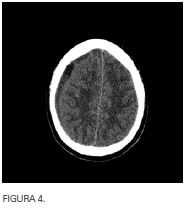

Paciente varón de 39 años sin antecedentes personales de interés que ingresa por sinusitis complicada clínica y radiológica (figura 1) de tres semanas de evolución que presenta cefalea frontal intensa que no mejora con tratamiento antibiótico, corticoideo tópico y sistémico. Tras cinco días de ingreso con tratamiento intravenoso comienza con aumento de la cefalea frontal y fiebre por lo que se realiza nuevo TAC de senos paranasales (figura 2) en el que se aprecia sinusitis frontal y etmoidal bilateral con un pequeño empiema epidural frontal derecho sin aparente dehiscencia ósea de la pared posterior de seno frontal ipsilateral.